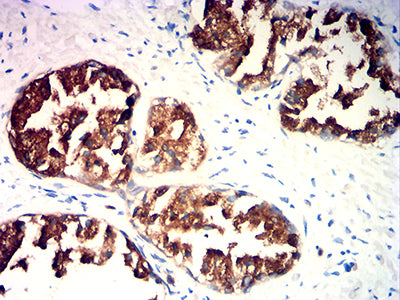

分类: 科研抗体货号: 32291别名: hK2; hGK-1; KLK2A2应用: IHC,IF,FCM反应种属: Human